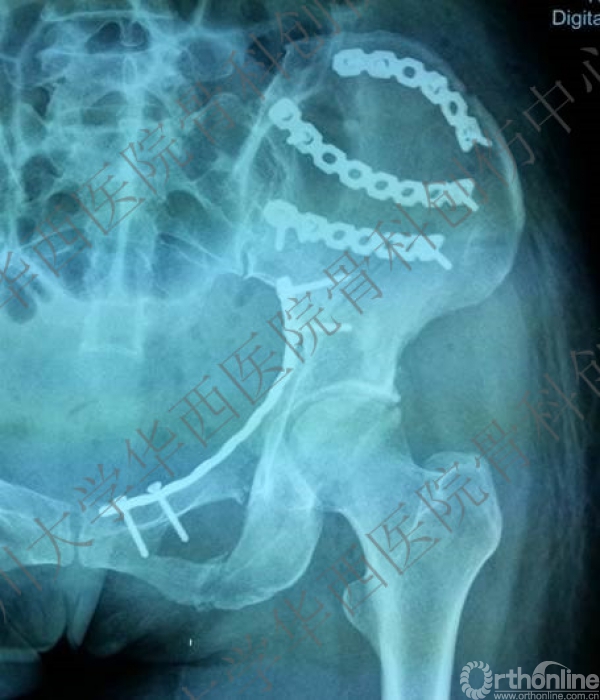

术后X线片

这是术后的X线片,患侧正位、髂骨斜位、闭孔斜位。

术后三维重建后面观,发现后壁的骨折有明显的移位,后脱位的风险增加,我们决定!

3天后,行后路切开复位内固定术。

3年后随访

3年后随访满意。